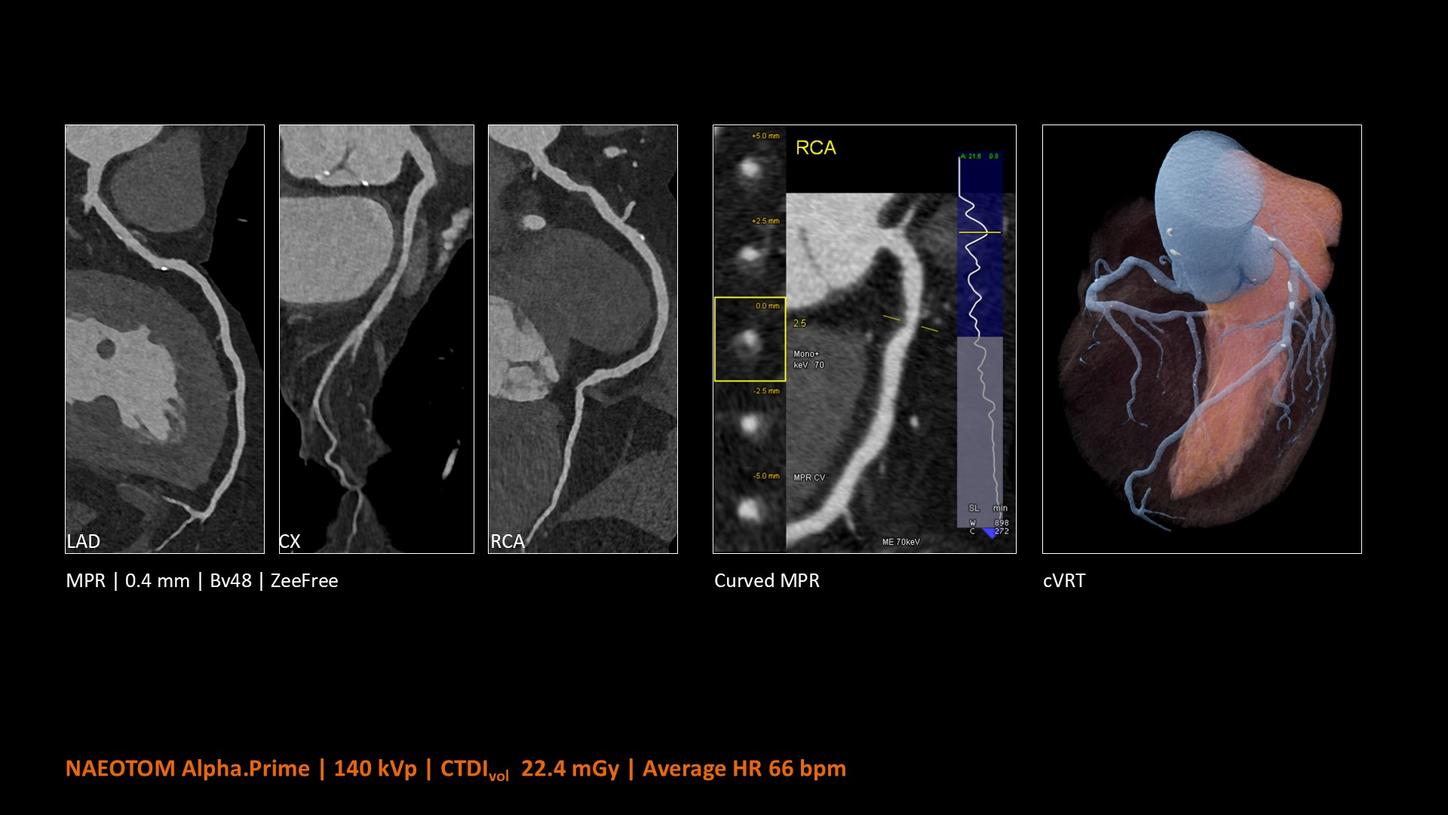

NAEOTOM Alpha® con Quantum Technology®, la nostra nuovissima Dual Source photon-counting CT, offre immagini Quantum HD Cardiac con uno spessore di slice di 0,2 mm. In questo modo è possibile visualizzare dettagli del cuore precedentemente non rilevabili senza incrementi di dose. Inoltre, le informazioni spettrali sono automaticamente disponibili in ogni scansione grazie a un processo di conversione diretta che trasforma i singoli fotoni dei raggi X in un segnale elettrico per creare l'immagine.

Il Dott. Bálint Szilveszter, MD, PhD, presso la Semmelweis University a Budapest, in Ungheria, condivide I benefici dell’elevata risoluzione spaziale e della valutazione della placca con la TC photon counting e come questi permettano una maggior confidenza diagnostica nella valutazione dei disturbi alle coronarie (CAD)